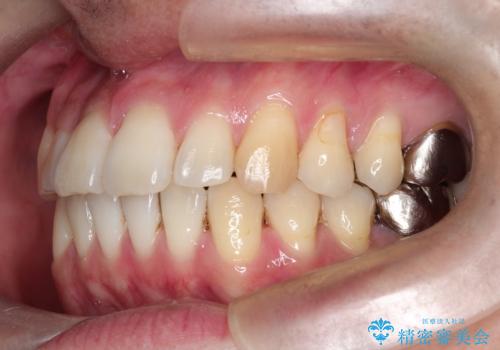

- 前歯の出ているのが気になる、下唇を噛んで痛いとのことで来院された患者様です。マウスピース矯正をご希望でした。

奥歯の噛み合わせはしっかりしていましたので、奥歯の動きは最小限にし、前歯の並びに集中した治療計画+インビザラインのシミュレーションを作成しました。

奥歯の噛み合わせは整っていたため、前歯の並びを美しく修正することに専念できました。マウスピース矯正による治療で短期間で改善しました。